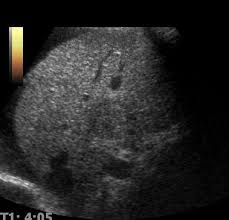

간 관련 질환

- 지방간: 간 조직 내 지방 축적 상태 확인 가능

- 간경화: 간 표면의 거칠음, 크기 변화, 비장 비대 여부 등 확인

- 간암, 간종양: 실질 내부에 덩어리 유무 탐색